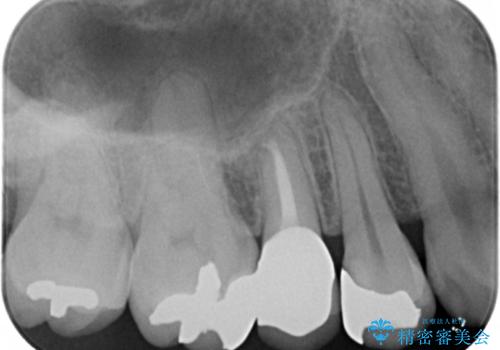

欠けている奥歯(左上5)は失活歯で、保険内の銀の詰め物(メタルアンレー)で治療されていました。

精査したところ、右上の奥歯(右上5)に根尖病変を認めたため、こちらは根管治療後にセラミッククラウンによる補綴を行いました。